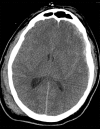

Case report: In this case report, we demonstrate the unanticipated recovery of a 28-year-old male patient who presented with a severe traumatic brain injury after being in a motorcycle accident without wearing a helmet. He presented with several exam and imaging findings that are statistically associated with increased mortality and morbidity.